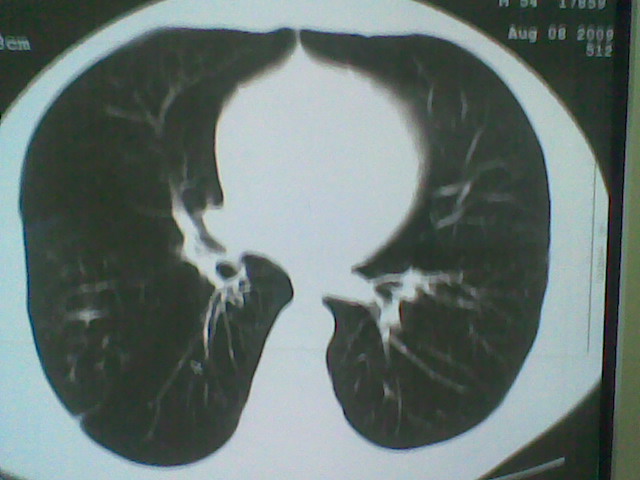

标题: CT21512:支扩伴感染?

患者女。咳嗽数天,咯血半天。

我们报的是支扩伴感染?

支持 支气管扩张并感染。

支持楼主意见,考虑支气管扩张并感染。

支气管扩张并感染。